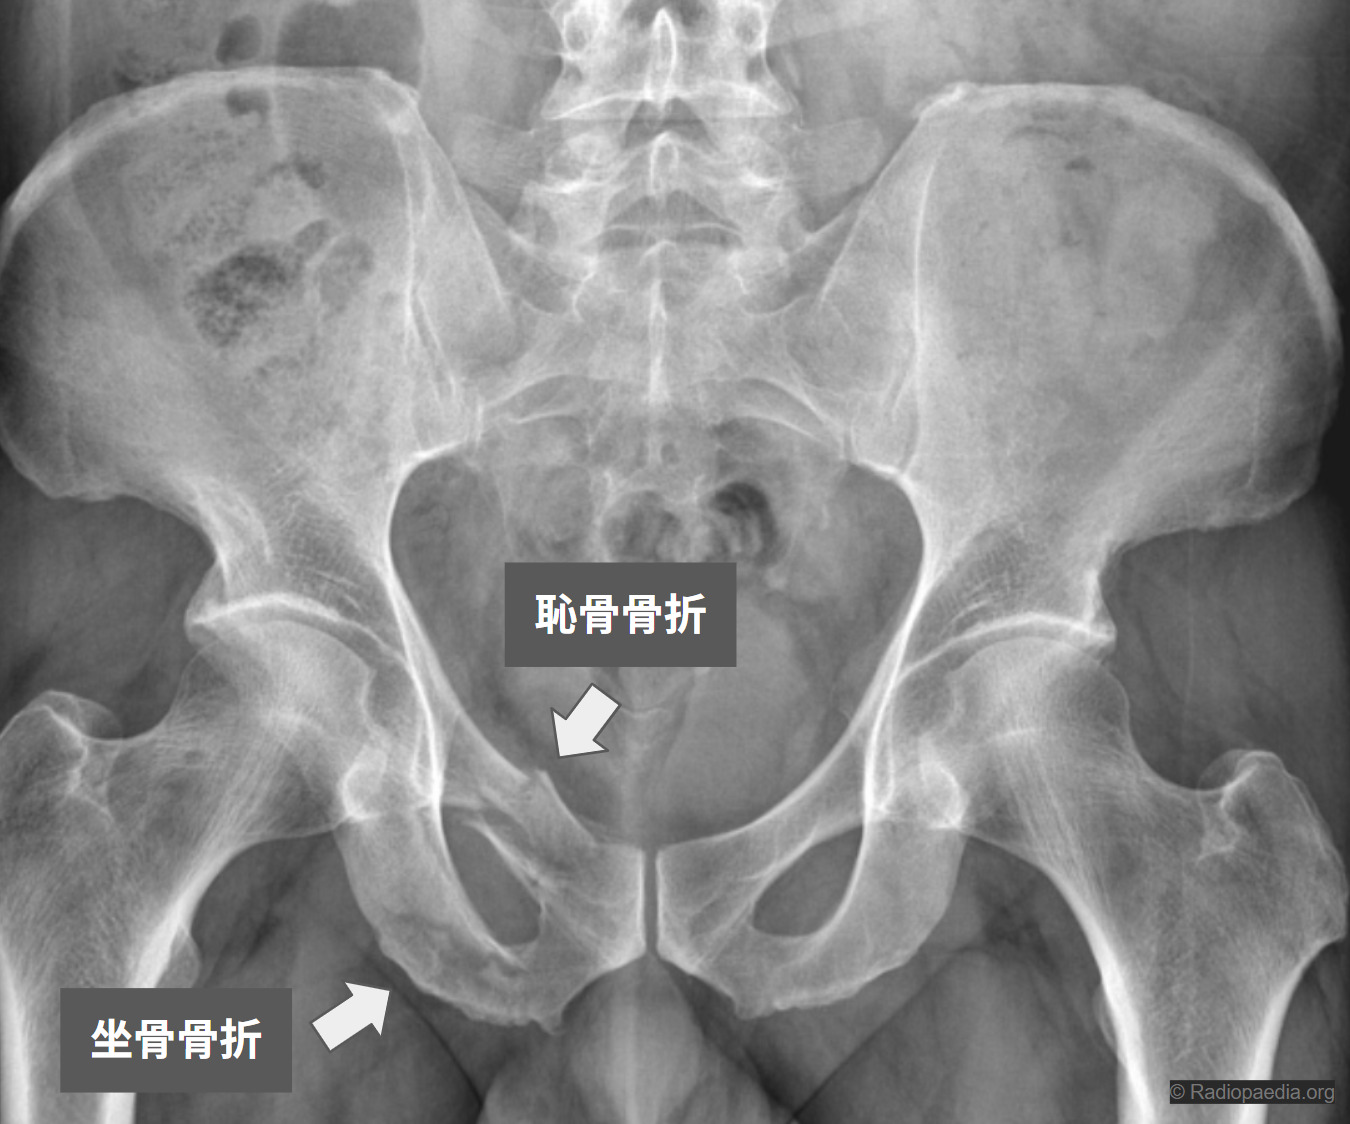

恥骨骨折・坐骨骨折

骨盤は仙骨・尾骨・寛骨(腸骨・坐骨・恥骨)が組み合わさった頑丈な「リング状」の構造で、背骨の土台として体を支えています。このリングの一部である恥骨や坐骨の骨折は、骨粗しょう症による脆弱性骨折(尻もちなどで発生)と、交通事故などの高エネルギー外傷による骨折に大別されます。

基本はレントゲン(単純X線)です。正面像に加えて、骨盤を斜めからみる Inlet(インレット)像・Outlet(アウトレット)像 も撮ることで、前側の恥骨枝の骨折は比較的見つけやすくなります。ただし、骨盤の後ろ側(仙骨など)の損傷はレントゲンだけでは見逃されることがあるため、脆弱性骨盤輪骨折(FFP)が疑われる場合はCT検査が重要です。